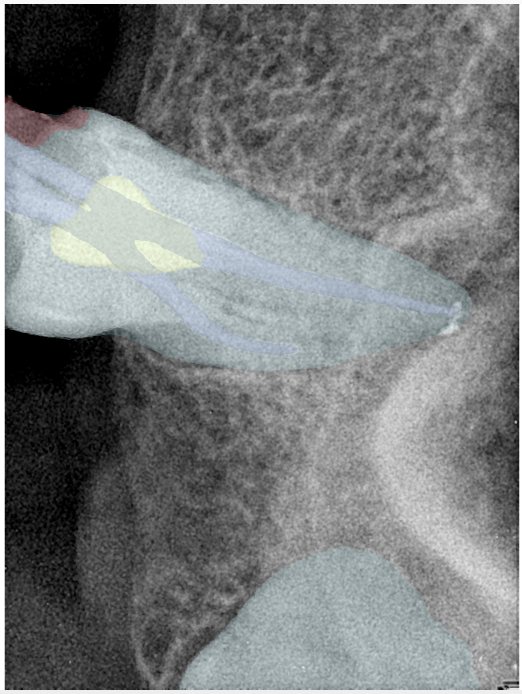

第二版算法问题测试

Updated: 2026-04-13(更新日期)

| 第一版 | 第二版 | 是否解决 | |

|---|---|---|---|

![]() | ![]() ![]() 边角识别有问题 龋齿识别不全 牙髓识别不全 | ![]() | 解决 |

![]() | ![]() 边角识别有问题 识别信息有误 自查(牙冠识别不全) | ![]() | 解决 |

![]() | ![]() ![]() 边角识别有误 大范围填充识别遗漏 | ![]() | 解决 |

![]() | ![]() 识别信息不全 | ![]() | 解决 |

![]() | ![]() ![]() 边角问题 牙胶识别不全 牙冠识别不全 | ![]() | 解决 |

![]() 换图片 | ![]() | ![]() 牙冠部分稍微白了一些就识别成小范围修补,部分判断异常 | 部分解决,修复类略敏感,牙冠部分稍微白了一些就识别成小范围修补,部分判断异常。 |

![]() | ![]() ![]() 牙冠识别不全 牙髓不全 根尖炎龋齿识别有误 | ![]() | 解决 |

![]() | ![]() | ![]() | 解决 |

![]() 换图片 | ![]() | ![]() | 解决 |

![]() | ![]() 牙冠识别有误 | ![]() | 解决 |

![]() 换图片 | ![]() ![]() 边角识别有误 | ![]() 修复类敏感 | 部分解决,图像过白,导致修复类判断异常。 |

![]() 换图片 | ![]() 牙冠识别不全 | ![]() 修复类敏感 | 部分解决,图像过白,导致修复类判断异常 |

结论:修复类出现了不鲁棒的情况,后续需要加入轮廓的扩充数据进行增强。